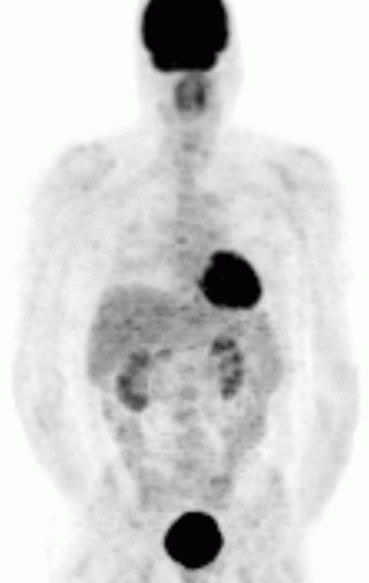

영상 검사로는 CT, MRI, 131I-MIBG 신티그래피, PET 등이 있다.[82] CT와 MRI는 종양의 위치, 크기, 주변 구조와의 관계를 파악하는 데 유용하다.[82] 131I-MIBG 신티그래피는 부신 외 원발 병변이나 전이 병변의 위치를 확인하는 데 사용된다.[88] MIBG는 노르에피네프린과 유사한 구조를 가져 종양 세포에 섭취되는 원리를 이용한다. PET 검사는 MIBG 섭취가 없는 경우에도 양성으로 나타날 수 있으며, 전이 병변 검색에 유용하다.[90] 특히, 68Ga-DOTA 유사체를 이용한 PET 검사는 소마토스타틴 수용체 영상 기법으로, 다른 기능적 영상 검사보다 우수한 성능을 보인다.[94][95][97]

전이성 크롬친화세포종은 종양 세포(크롬 친화 조직)가 정상적으로 발견되지 않는 곳에 존재하는 것으로 정의된다.[133] 가장 흔한 부신 외 전이 부위는 림프절, 폐, 간, 그리고 뼈이다.[135]